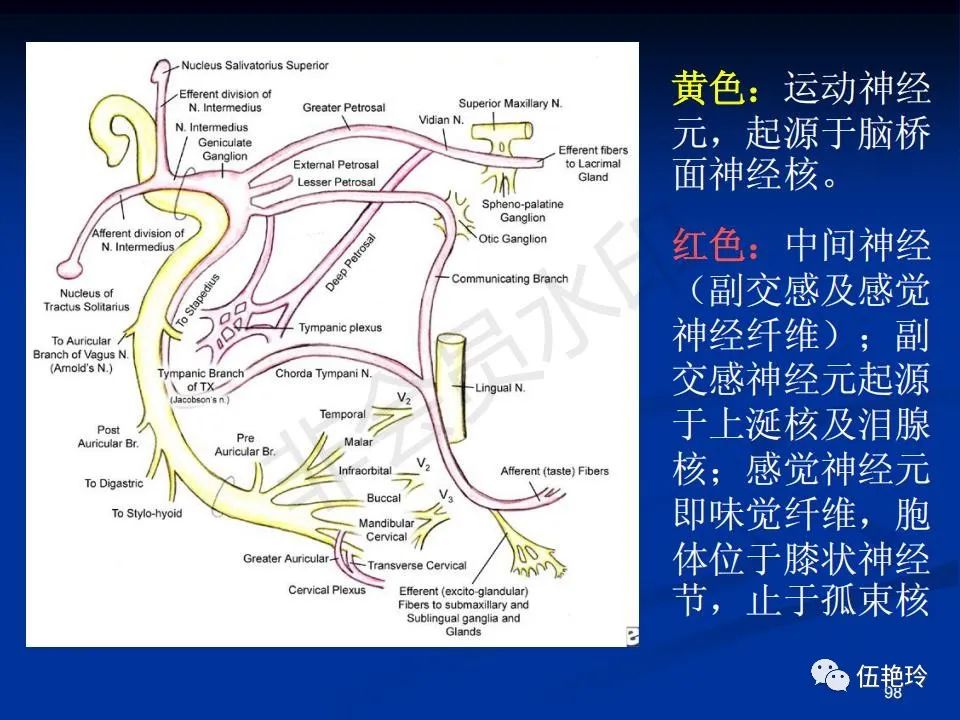

耳与面神经的解剖